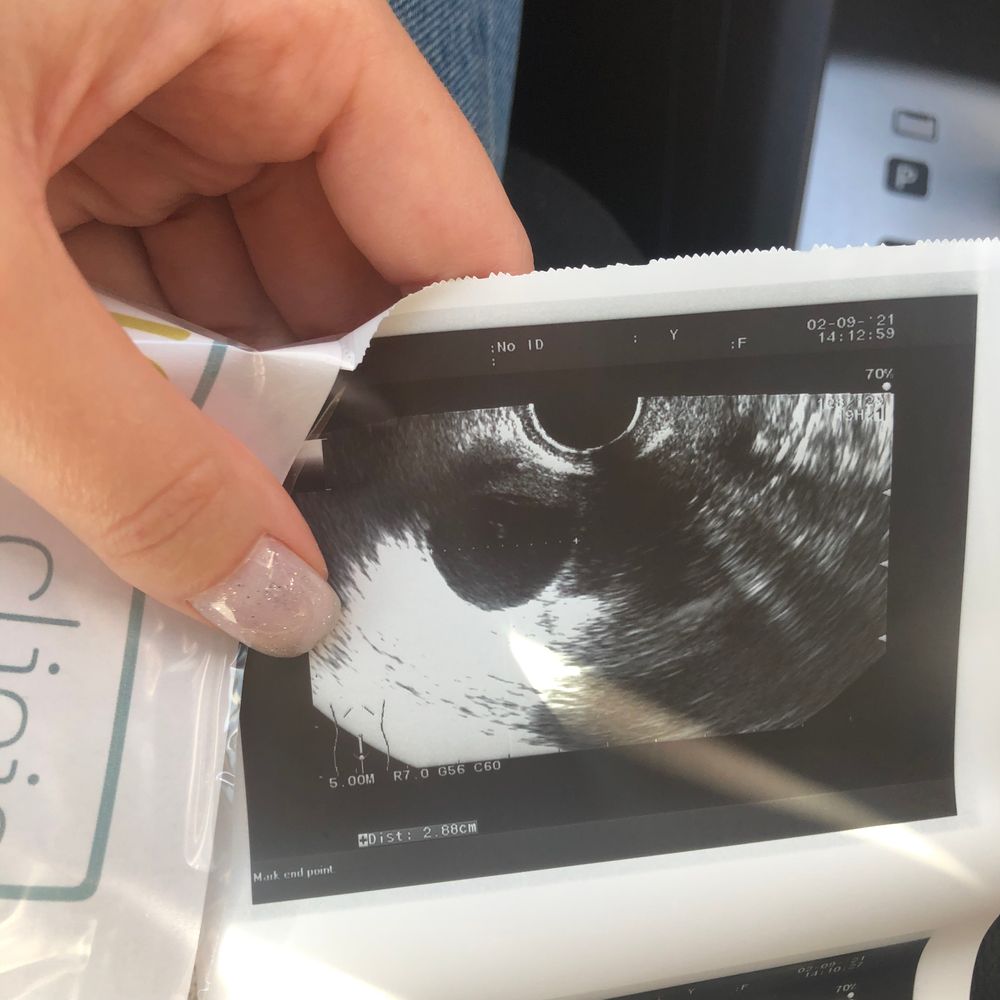

Может у кого-то было такое, но О всё же была? 16ДЦ, тесты полосатили на 13-14ДЦ, сегодня подросла БТ. А на узи - персистирующий фолликул почти 30мм🤥

Г сказала, что есть маааленькая вероятность того, что это ЖТ заполненное водой, отправила сдать прогик. Думаю, если бт завтра упадёт , или не вырастет - то нет смысла прогик сдавать? Эндик всего 8мм;(

Скоро два раза мама!!!))), а есть фото? У меня сейчас тоже по вопросом жт или фоликул лютинизировался. Узист под вопросом поставила.

Женя Ветлова, у меня больше на жт похоже чем на дф, у вас на дф,размер 26 мм и тоже бт второй фазы.

Мила, нет, фото нет. На экране только видела. Очень похоже на ЖТ, зернистое такое, серое. А тут у девушки больше на обычный фолликул похоже.

Скоро два раза мама!!!))), а на мое похоже? Фото выше? Вот думаю что это?))